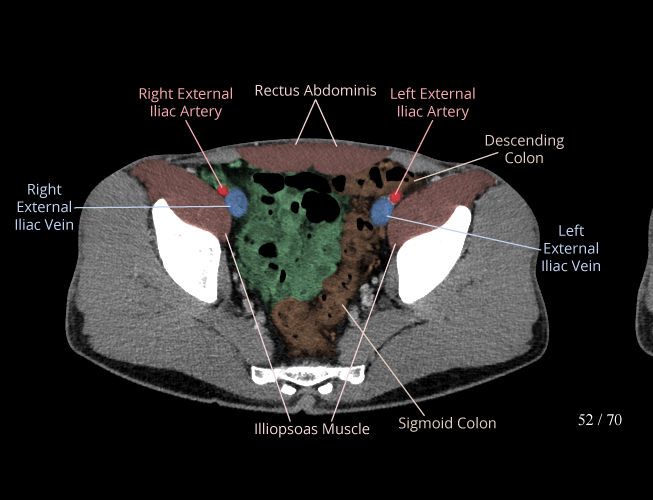

Body

Covers abdominal CT anatomy.